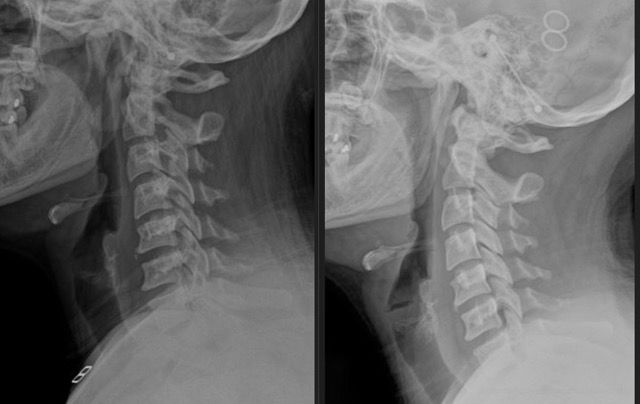

What happens if I ignore this problem? Here is an example of two x-rays taken of the same person 11 years apart with no treatment. It doesn't magically get better. It keeps getting worse.

We use detailed X-rays to measure the exact position of your head in relation to your spine. This gives us a clear starting point and allows us to track your improvement with objective measurements.

We take follow-up X-rays to show you exactly how your spine is changing. The images don't lie - you'll see real structural improvement, not just temporary relief.

Our before and after X-rays show dramatic improvements in neck curve and head positioning. What many people think is a permanent problem can actually change with the right care.